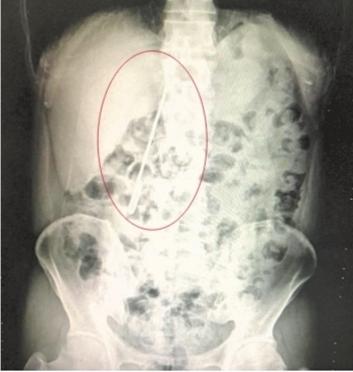

常先生腹中的毛衣针清晰可见

CT显示,毛衣针在常先生十二指肠拐弯处已穿透肠壁,尖端外露,有进一步损伤大血管及结肠的风险。医生立即为常先生实施手术,切开胃部取出毛衣针,并修补好十二指肠破口。